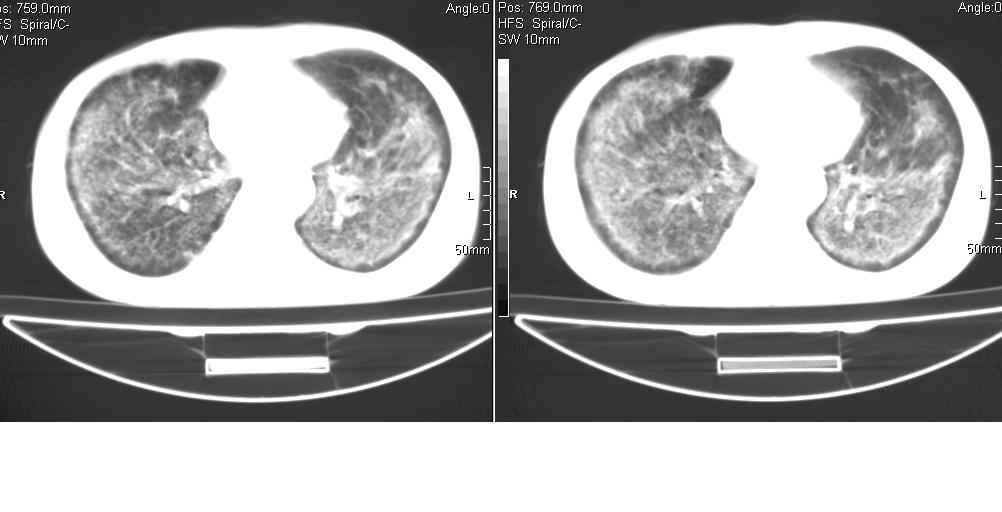

以下是引用光线在2008-5-6 18:36:00的发言:[br]双肺结核(左上肺空洞形成)、间质性改变合并感染,右肺大泡;右侧胸膜增厚。

以下是引用zsl6918在2008-5-7 1:54:00的发言:[br]首先肺泡蛋白质沉着症,其次考虑机遇性感染。